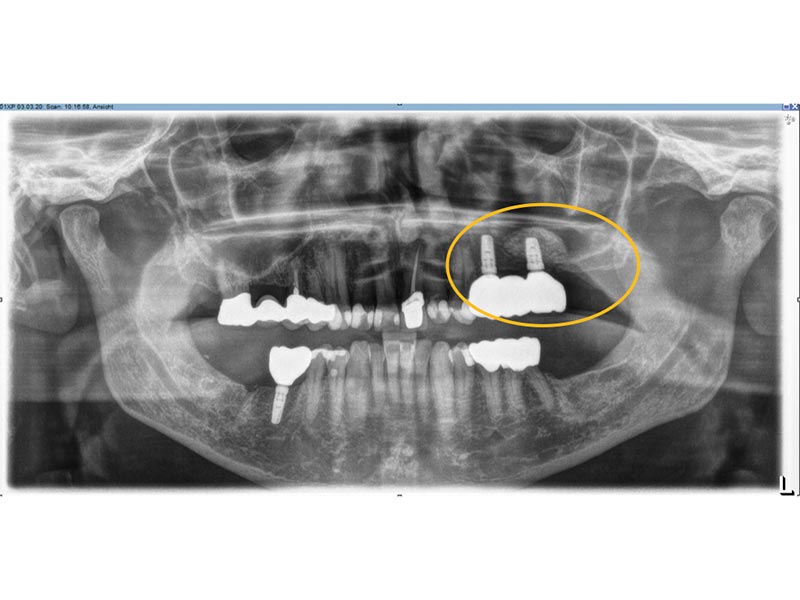

Zahnimplantate werden anhand von moderner virtueller 3D-Planung passgenau geplant und inseriert. Der Vorteil von Implantaten besteht darin, dass festsitzender ästhetischer Zahnersatz auch in solchen Fällen realisiert werden kann, in denen sonst nur herausnehmbare Prothesen möglich wären. Zudem ist im Gegensatz zur Brückenprothetik kein Beschleifen der Nachbarzähne notwendig.

Unter dentalen Implantaten versteht man im allgemeinen eine Schraube, die dort, wo ein oder mehrere Zähne verloren gegangen sind, in den Kieferknochen "eingepflanzt" wird. Diese Therapieform der Implantologie hat sich in den letzten Jahren zu einem alltäglichen Therapieverfahren in der Zahnheilkunde entwickelt. Wissenschaftliche Untersuchungen zeigen hierfür eine Erfolgsquote von i. d. R. 80-98 % über 10 Jahre. Verglichen mit anderen zahnärztlichen Maßnahmen gibt es nahezu keine andere Therapie mit derart guten Erfolgsaussichten. Auch eine Verbesserung der Lebensqualität wird durch implantatgetragenen Zahnersatz laut klinischer Studien erreicht.

Mittlerweile hat sich die Implantologie zu einem alltäglichen Therapieverfahren mit sehr guten Erfolgsaussichten in der Zahnheilkunde entwickelt. Bei guter Mundhygiene und regelmäßigen Kontrolluntersuchungen können fachmännisch gesetzte Zahnimplantate ein Leben lang halten.